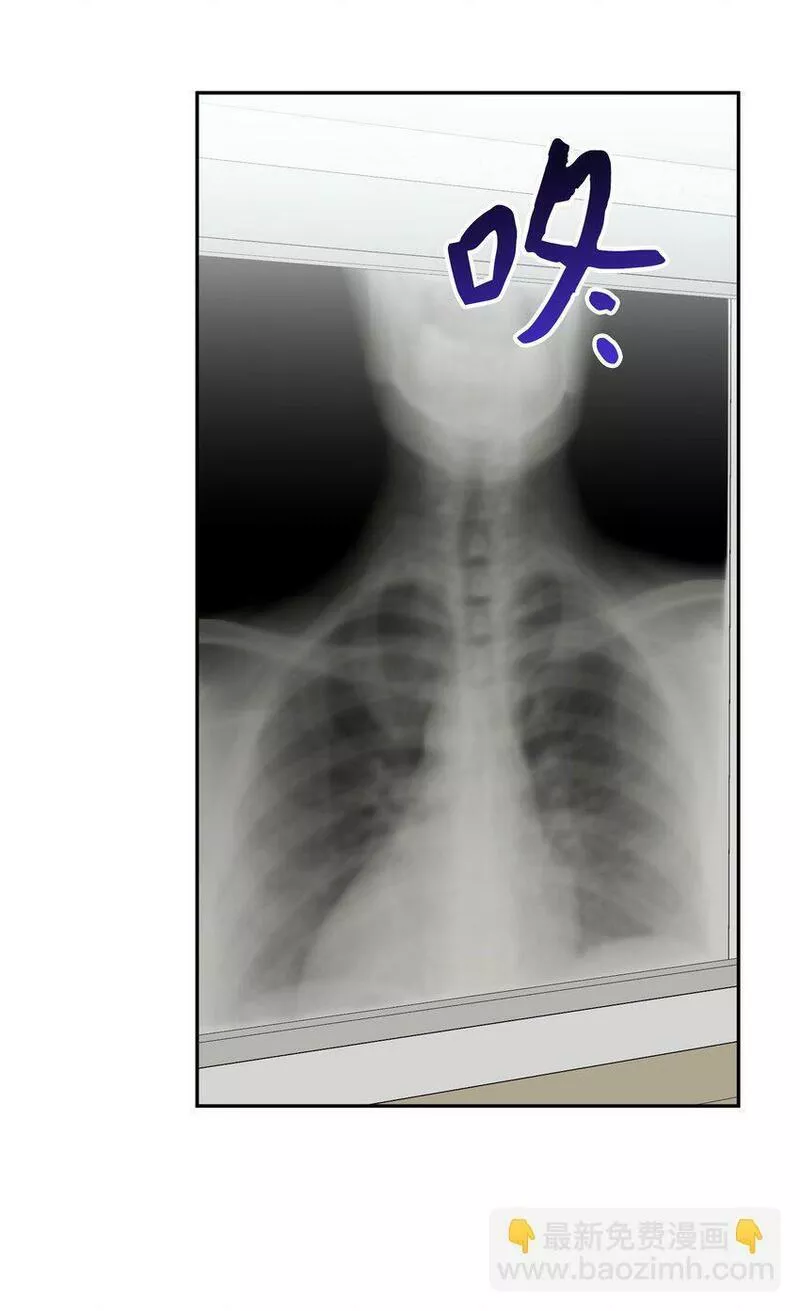

商界的天之骄子,冷酷男马逸鸣在一场车祸后成了依赖妻子的小奶狗。而表面上柔柔弱弱,人畜无害的舒颜,却在第一时间赶到医院,放弃救治丈夫副驾驶上的那个女人。失忆的丈夫,纠葛的情感,模糊的真相……这场本应走到尽头的婚姻,还能维持多久?两人能否放下芥蒂,回到最初?